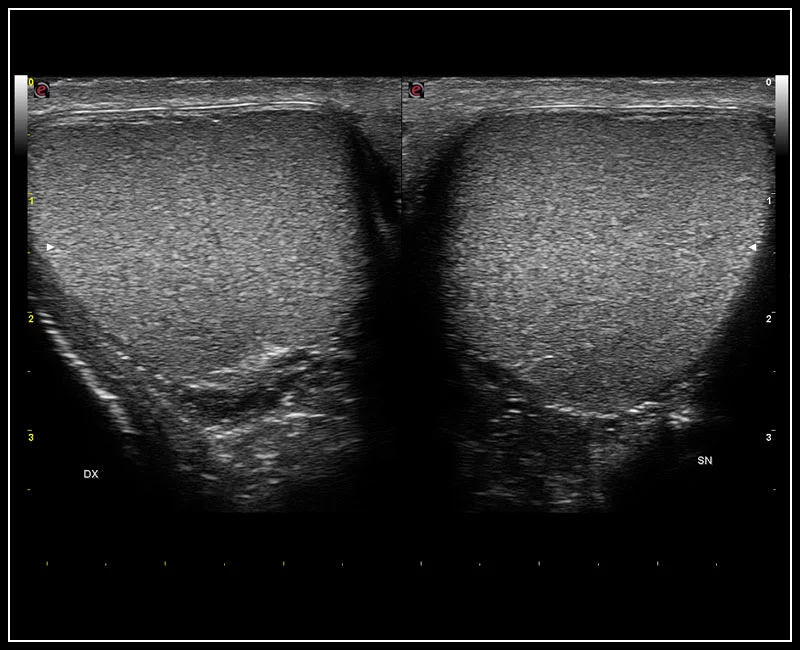

MyLab™9 Platform - High resolution imaging in testis

MyLab™9 Platform - High resolution imaging in testis